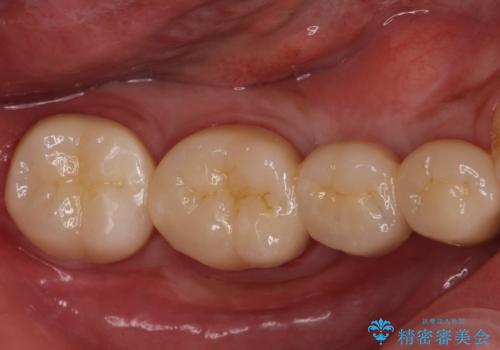

適合の良い被せ物、インプラントが入りました。

全ての治療が終わった後はNG(ナイトガード)を使用し、定期的にメンテナンスに

くることをお勧めしたいます。